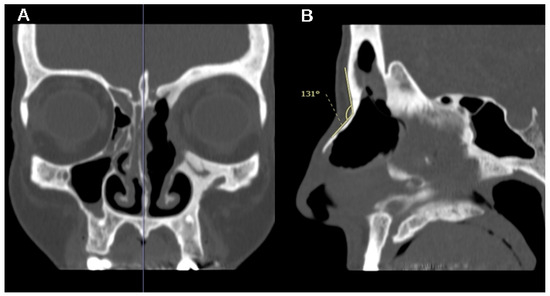

Figure 4.

A patient with left fronto-ethmoidal sinusitis with orbital involvement undergoing a DRAF III surgery. On the coronal CT-scan, the mid-sagittal plane is identified by the location of nasal septum and crista galli (blue vertical line in (A)); the angle between the glabella and nasion (G-N angle) is then calculated on exactly these mid-sagittal sections (B).